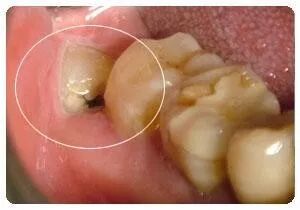

蛀牙:如果智齿蛀牙,除了简单的咬合面不深的蛀牙可以补之外,那些邻接面蛀牙,需要很好的技术,以及蛀的很深,甚至需要根管治疗的,我们建议拔除,杜绝后患。

清洁不易:由于空间不足的关系,智齿长得歪七扭八,因此常造成清洁牙齿的困难,以致发生蛀牙的现象。